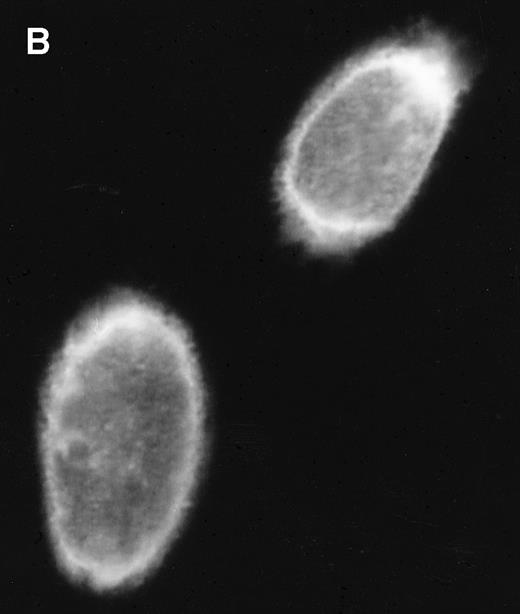

Several putative ORFs are identifiable in BART cDNAs. The distal RK-BARF0 ORF has recently been shown to express a 30-kD protein in transfected cells and the RK-BARF0 protein has been reported to be present in EBV-positive B-cell lines and in tumor specimens.33 A proximal ORF, RPMS1, has also been described40 and transcripts with splicing consistent with that described for the cDNA containing RPMS1 were detected in CD19+ peripheral blood B cells. The protein product of the RPMS1 ORF was examined using a vector that expressed RPMS1 tagged with the Flag epitope. In cells transfected with Flag-RPMS1, a protein of approximately 15 kD was detected by Western blotting with anti-Flag antibody (Fig 6A). Indirect immunofluorescence assays using anti-Flag antibody showed that the RPMS1 protein localized to the nucleus of transfected cells (Fig 6B). Thus, the BART family of RNAs has the potential to encode at least two independent proteins.

RPMS1 protein expression. (A) Western blot analysis of 293T cells transfected with an expression vector containing the Flag-tagged RPMS1 ORF. The Flag-RPMS1 protein band detected using anti-Flag mouse MoAb is indicated by an arrow. The relative positions of the molecular weight markers are shown on the left. Lysate of nontransfected 293T cells was used as the control. (B) Indirect immunofluorescence assay showing Flag-RPMS1 expression in transfected Vero cells. Flag-RPMS1 was detected using anti-Flag MoAb and FITC-conjugated secondary antibody.